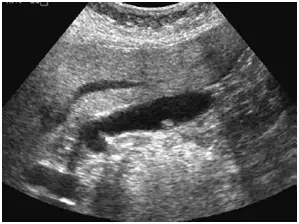

下列腹部超音波影像診斷最可能為:

超音波影像顯示膽囊腔內可見一枚小型、高回音性(hyperechoic)結節狀病灶,附著於膽囊壁並突入管腔。關鍵影像特徵如下:

- 無後方聲影(no posterior acoustic shadowing):這是與膽囊結石最重要的鑑別點;結石會產生明顯的後方聲影,而息肉不會

- 固著於膽囊壁(non-mobile, wall-attached):病灶不隨體位改變而移動,排除可自由滾動的結石

- 膽囊壁無明顯增厚:不符合急性膽囊炎的超音波表現(後者通常有壁厚 > 3 mm、膽囊周圍積液、超音波墨菲氏徵 Murphy's sign)

- 無 Rokitansky–Aschoff sinuses(RAS) 所產生的彗星尾偽影(comet-tail artifact):排除膽囊肌腺瘤

整體影像表現最符合膽囊息肉,尤以膽固醇息肉(cholesterol polyp)最為常見。